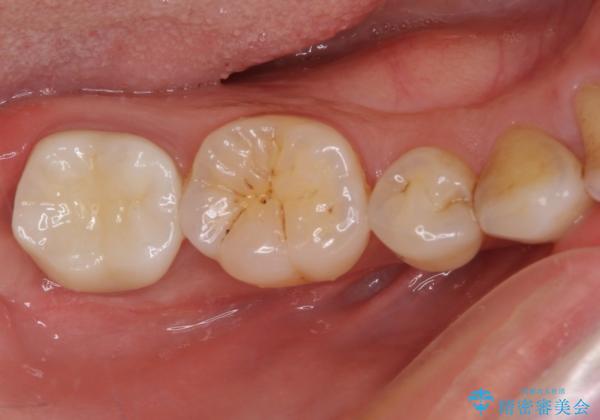

遠心の歯肉が盛り上がっていたため、清掃性が悪くなる懸念がありましたが、クラウン装着による歯肉の腫れは認められませんでした。